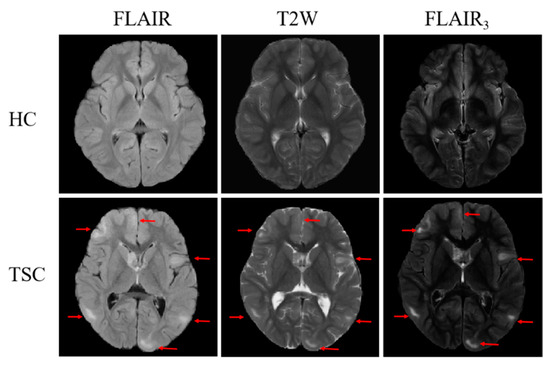

4.2. Visualization Results of FLAIR3